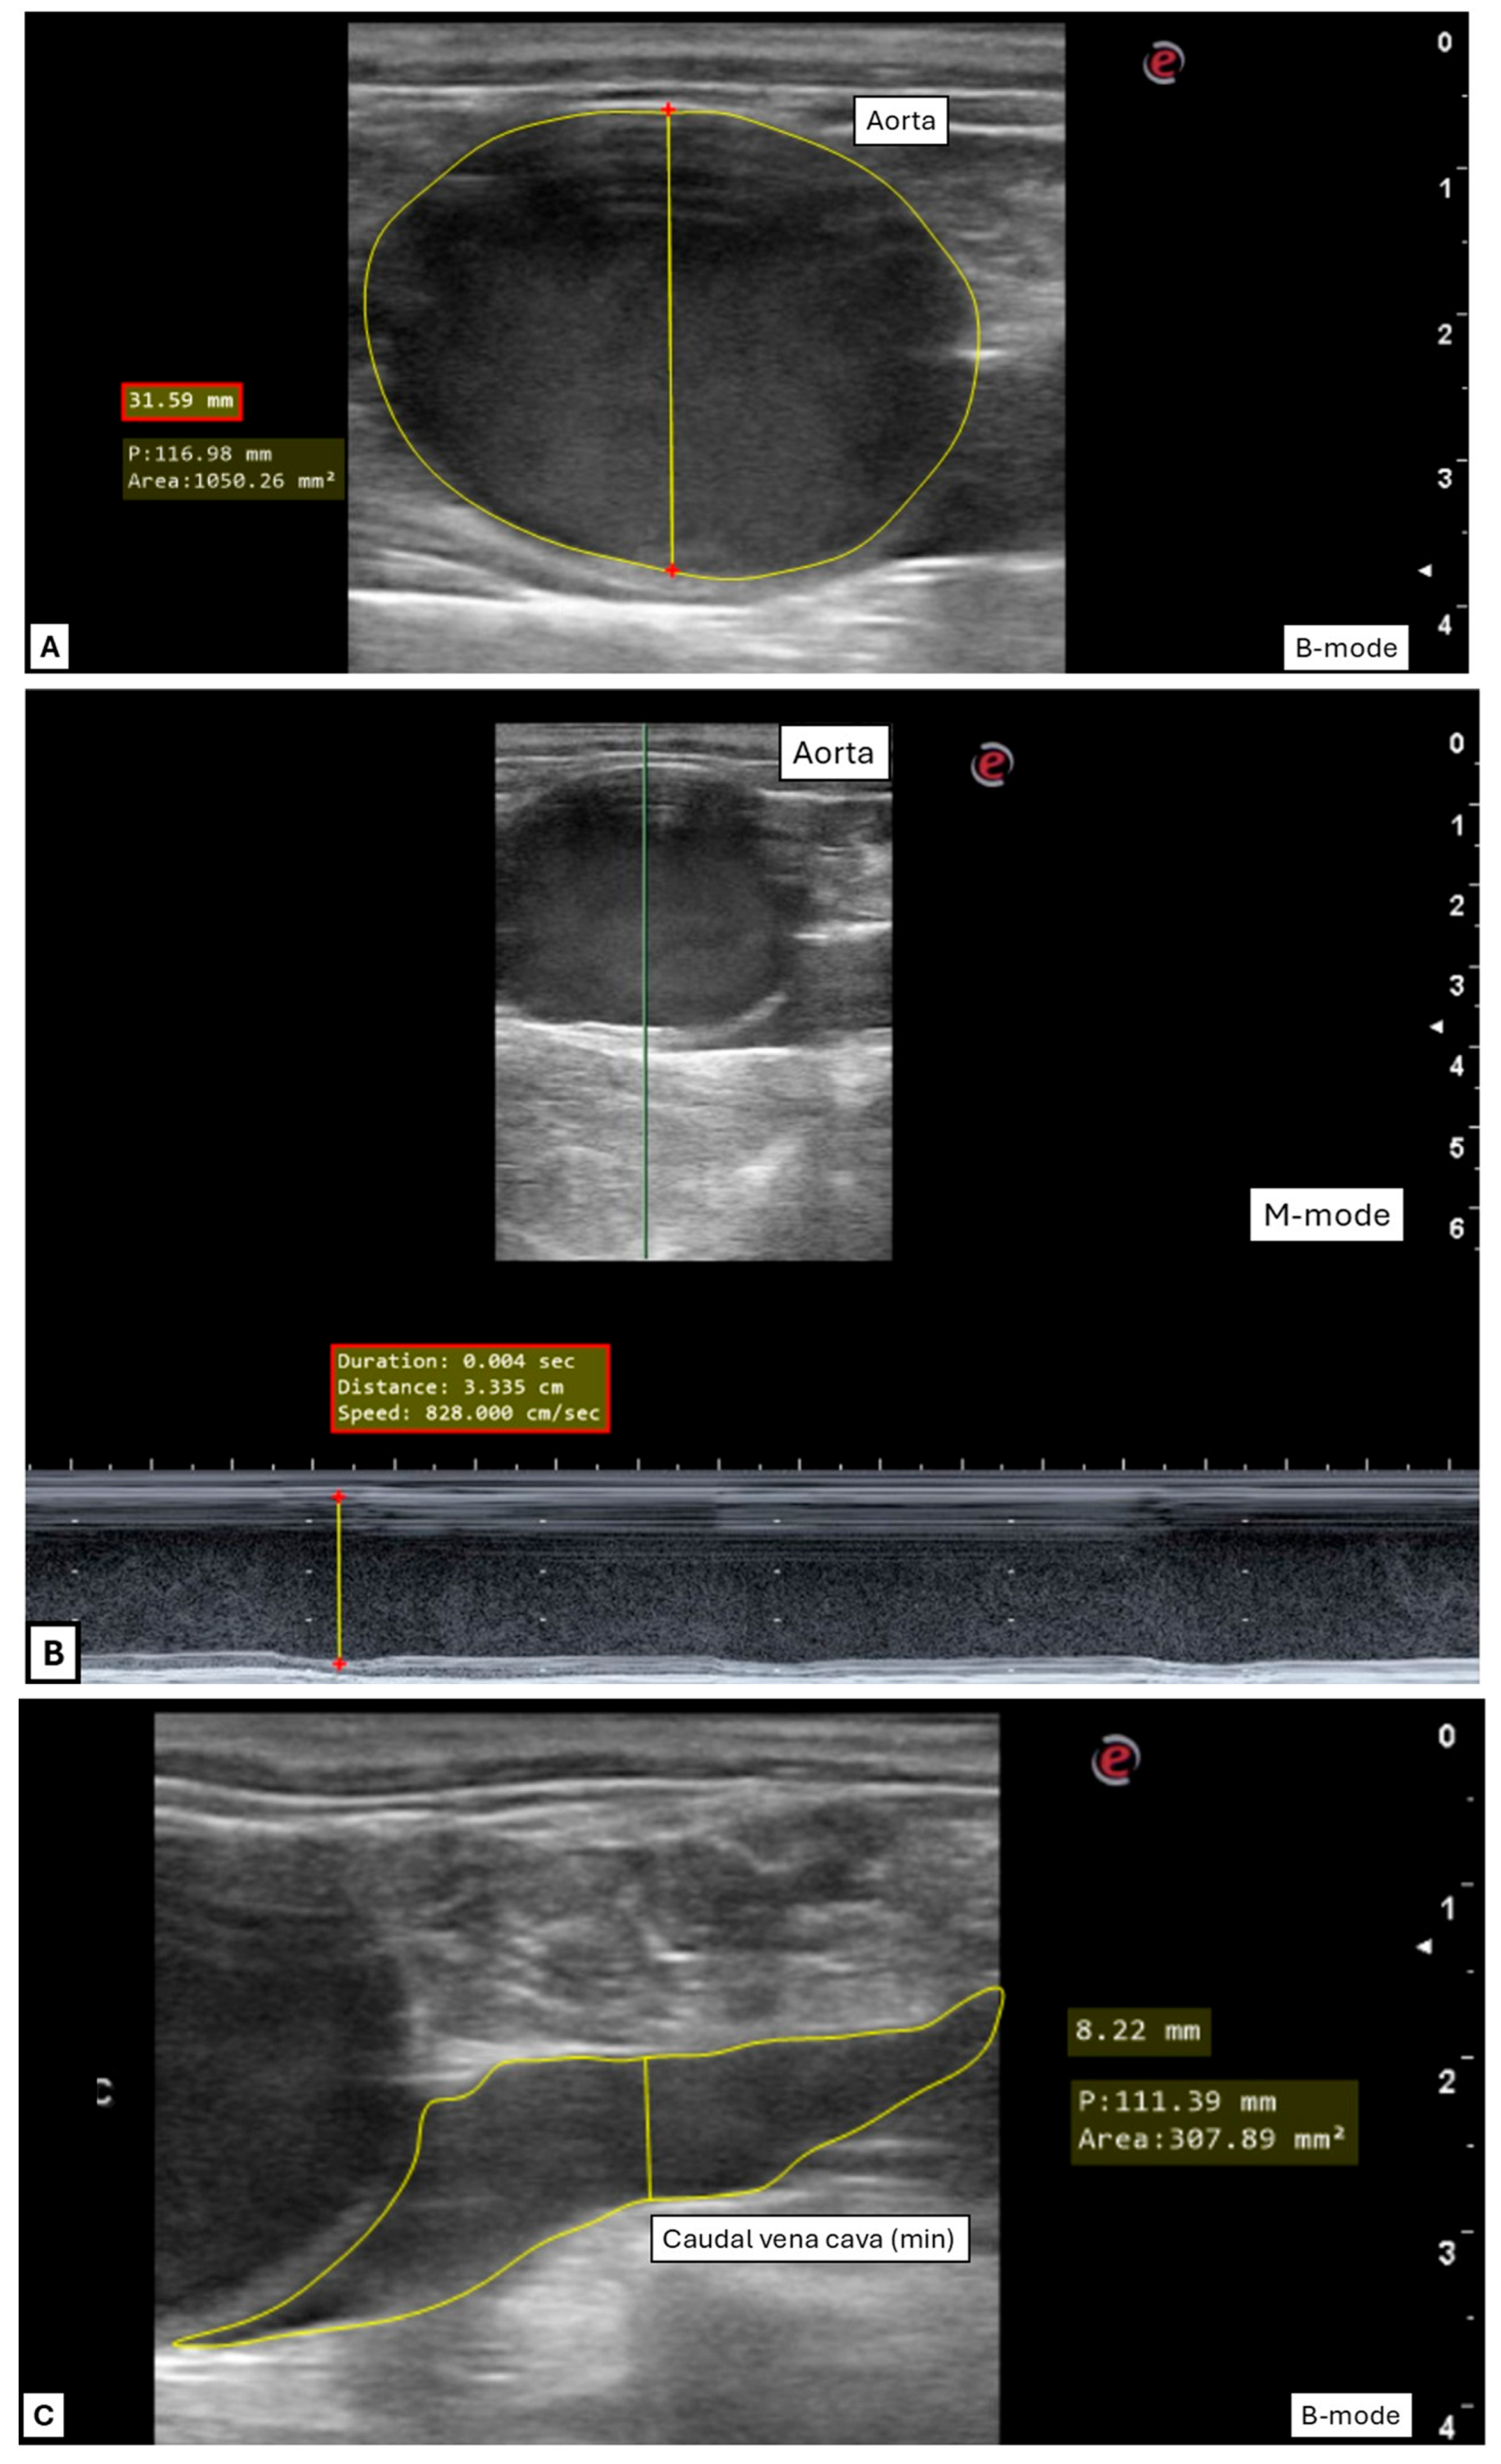

2.3.2. Transrectal Variables

3.2. Transrectal Variables